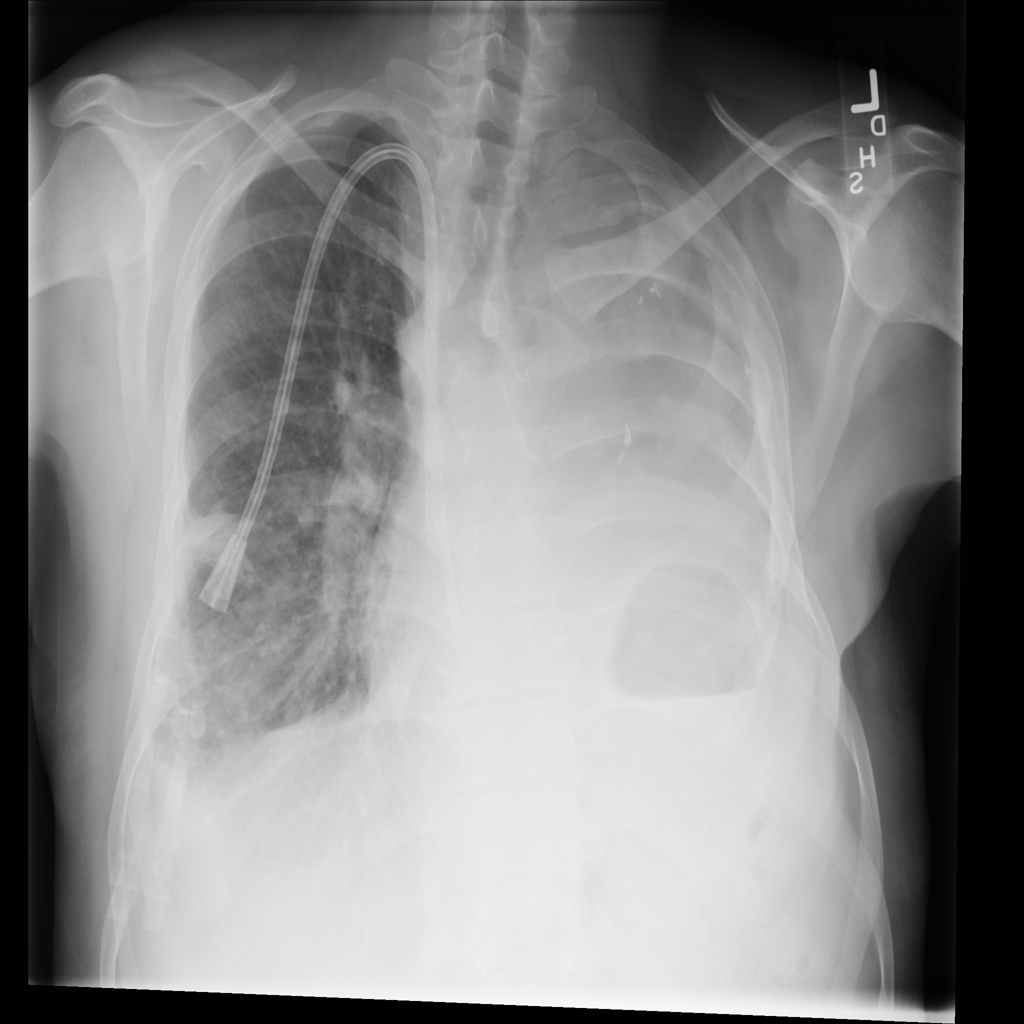

PAT-86C8 · IMG-000Effusion

PAT-86C8 · IMG-000

PA